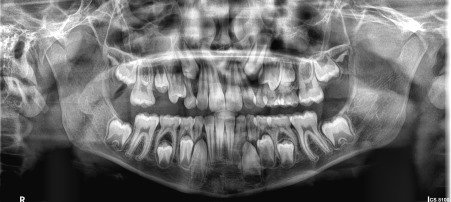

Examples of image quality using the Carestream 8100 3D